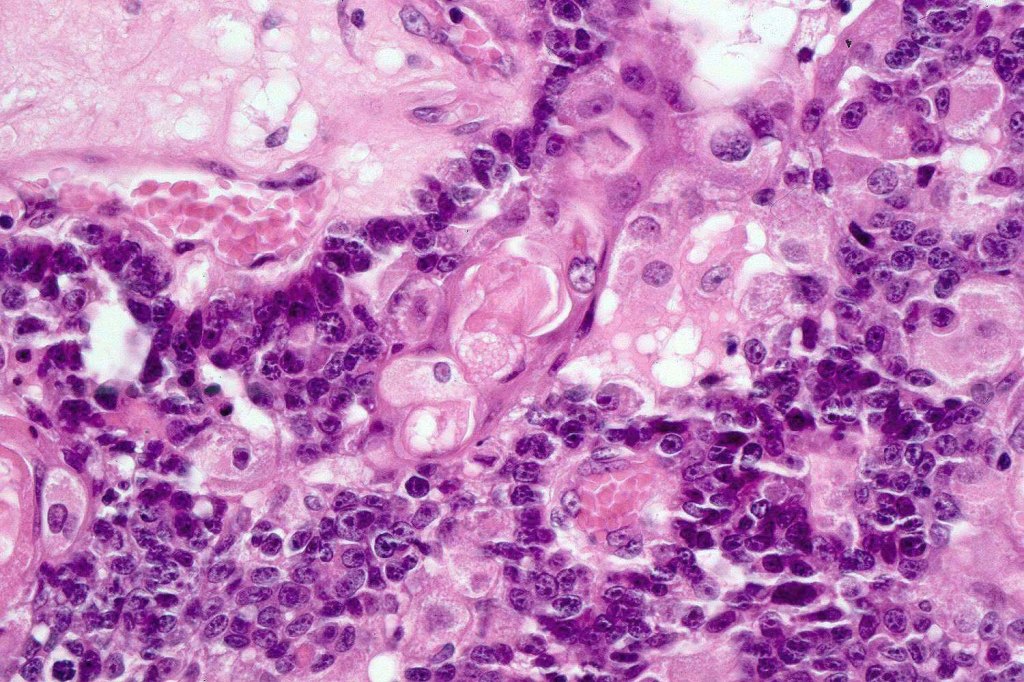

•Tumors are composed of an admixture of darkly staining basaloid cells with hyperchromatic or vesicular nuclei and more obvious sebaceous cells with eosinophilic, bubbly, multivacuolated cytoplasm frequently indenting the nucleus (scalloped)

•Often mitoses are numerous and abnormal forms evident

•Variable Lymphovascular invasion & perineural infiltration

•Focal squamous differentiation with keratinization can be present resulting in confusion with squamous cell carcinoma

Sebaceous carcinoma from a patient with Muir-Torre syndrome kindly shared by Dr. Antonina Kalmykova.